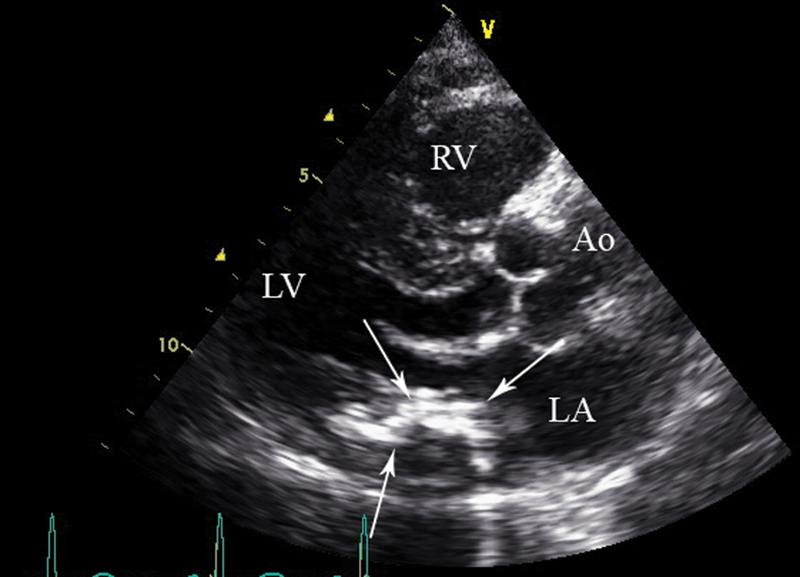

فحوصات تشخيصية لبعض امراض القلب والشرايين التاجية